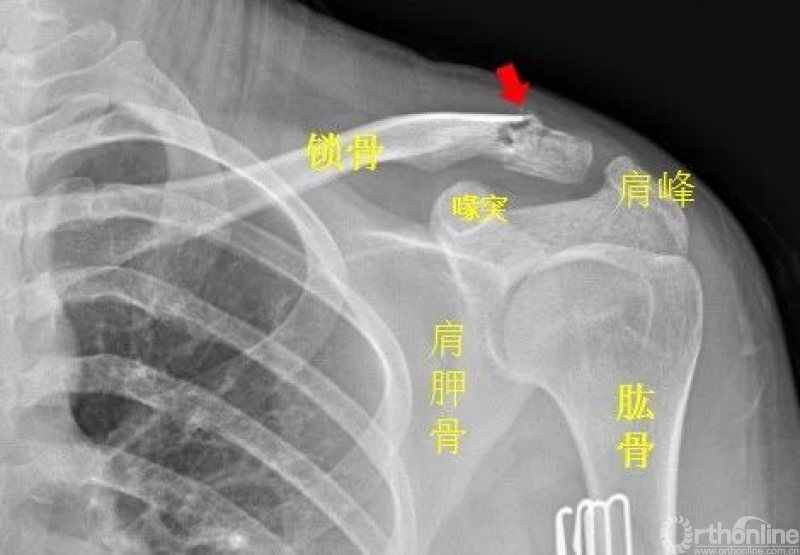

肩关节

左侧锁骨肩峰端见不规则透亮线,骨折处稍移位。左侧锁骨骨折